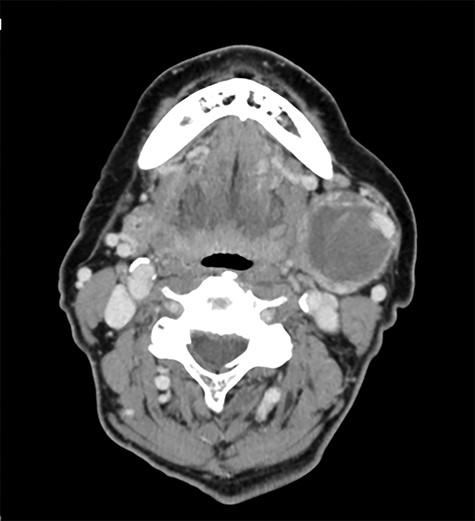

A 79-year-old female non-smoker presented with painless swelling below the left side of the mandible angle, which was first noticed 4 years previously (Fig. 1). She had no history of cardiovascular disease, diabetes mellitus and trauma to the head and neck. The palpable mass was pulsatile and had a diameter of 5 cm. Intraoral examination was unremarkable. A computed tomography (CT) (Fig. 2) and a magnetic resonance imaging scan demonstrated the presence of a 5-cm left submandibular gland tumor, whereas contrast-enhanced CT (Fig. 3) and ultrasonography revealed a 3.8 × 3.3 cm aneurysm of the facial artery with a cystic structure. We judged a submandibular tumor with pseudoaneurysm or a true aneurysm and suggested treatment options for the mass. The patient selected surgical excision under general anesthesia in response to the pathological diagnosis and to ensure the recovery of her esthetic appearance. We, therefore, consulted endovascular surgeons for angiography and internal trapping before the surgical excision, considering that there was a risk of bleeding during the operation.

Preoperative contrast-enhanced computed tomography with 3D reconstruction.